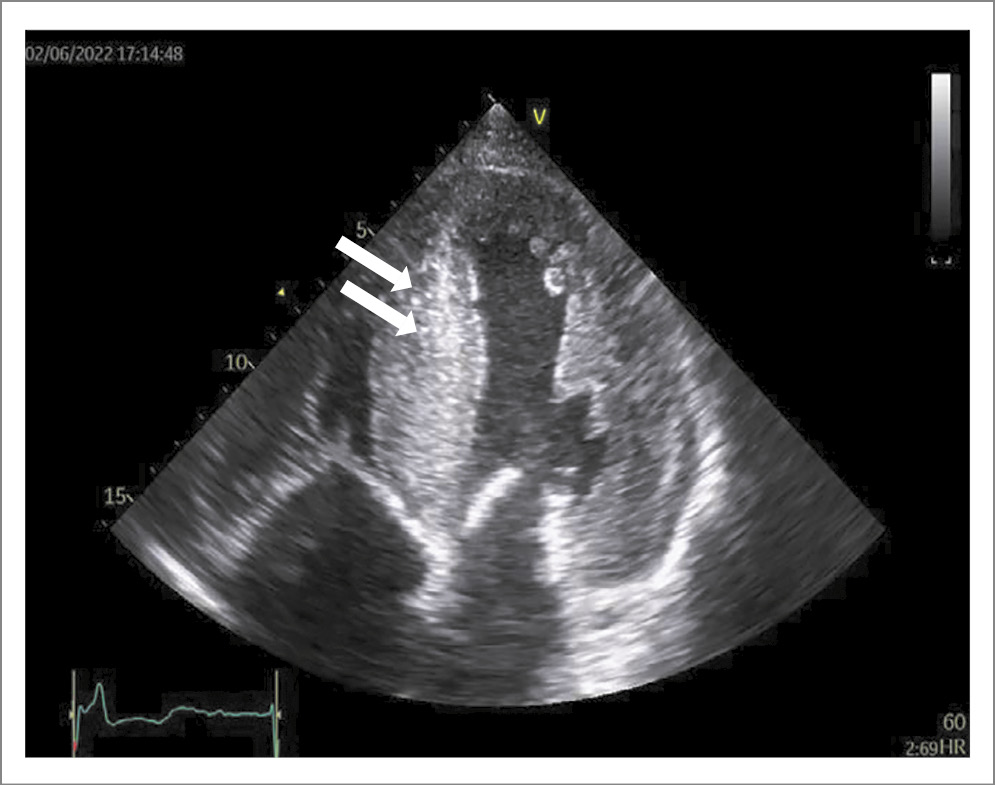

При ЭхоКГ (табл. 1) выявлено расширение полостей обоих предсердий, уменьшение полости ЛЖ, умеренное снижение глобальной сократимости ЛЖ, концентрическая гипертрофия миокарда ЛЖ, нарушение диастолической функции по рестриктивному типу с повышением давления наполнения 3-й степени. Выраженная «зернистость» миокарда (рис. 2). На основании совокупности таких признаков, как утолщение миокарда при отсутствии анамнеза артериальной гипертензии, рестриктивный тип нарушения диастолической функции, умеренное снижение глобальной сократимости сердца с незначительным уменьшением полости ЛЖ, «зернистости» миокарда, а также снижение вольтажа от стандартных отведений по данным электрокардиографии, была вынесена гипотеза о наличии АК.

Рис. 2. Двухмерная (B-режим) ЭхоКГ пациента П. Апикальное четырехкамерное сечение. Наблюдается значительное утолщение стенок ЛЖ с наличием мелких включений в межжелудочковой перегородке (указаны стрелками).